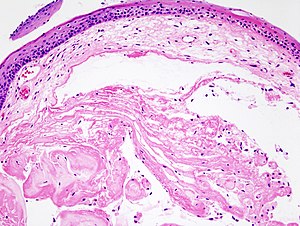

Microscopic

Features:[3]

- Early:

- Edema.

- Fibroblasts proliferation.

- Late:

- Subepithelial hyaline / stromal hyaline.

- Blood vessels - dilated.

Left Vocal Cord Polyp, Excision: - Stratified squamous epithelium with compact hyperkeratosis and stromal edema, consistent with benign vocal cord nodule or polyp. - NEGATIVE for malignancy.

VOCAL CORD LESION, EXCISION: - STRATIFIED SQUAMOUS EPITHELIUM WITH PARAKERATOSIS AND SUBEPITHELIAL HYALINE MATERIAL, CONSISTENT WITH WITH VOCAL CORD NODULE OR POLYP. - NEGATIVE FOR MALIGNANCY.